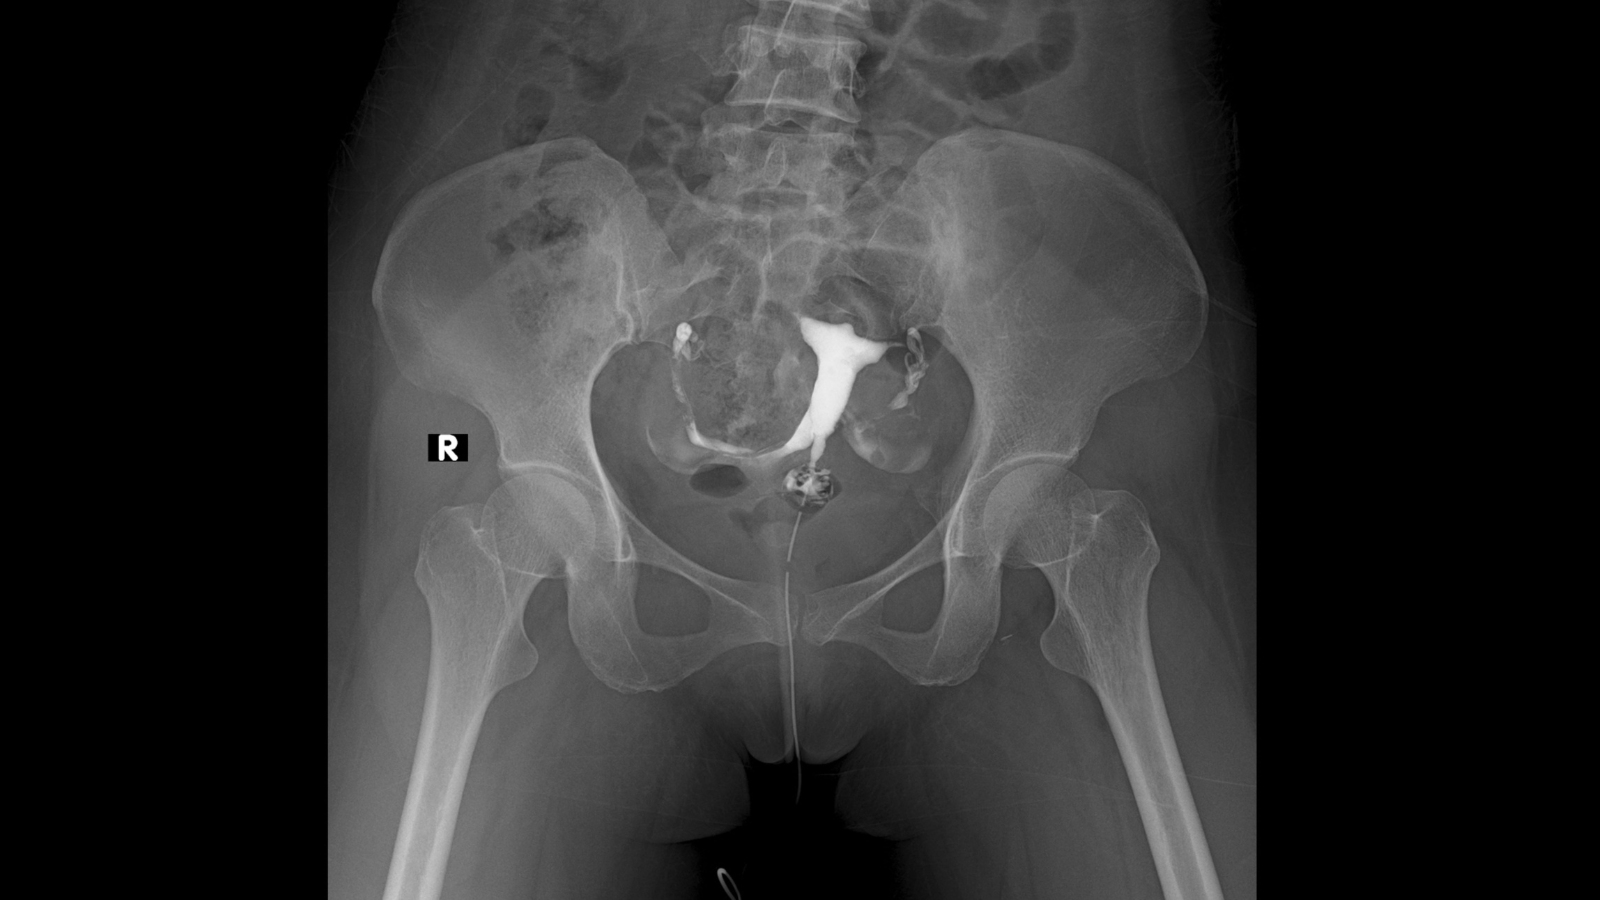

Quá trình chụp HSG diễn ra khá nhanh, thường chưa đầy năm phút và bệnh nhân có thể về nhà ngay trong ngày. Trong suốt thủ thuật, bác sĩ sẽ bơm dung dịch thuốc nhuộm vào tử cung và ống dẫn trứng, đồng thời chụp X-quang để ghi lại hình ảnh, từ đó đánh giá tình trạng của đường sinh sản.

- Tiêm thuốc nhuộm: Sau khi tháo mỏ vịt, bệnh nhân duỗi thẳng chân và dung dịch nhuộm được bơm từ từ vào tử cung. Trong quá trình này, có thể cảm thấy đau quặn, đặc biệt nếu ống dẫn trứng bị tắc. Bác sĩ có thể thay đổi tư thế bệnh nhân để quan sát rõ hơn sự di chuyển của thuốc nhuộm.

- Ghi nhận kết quả: Nếu ống dẫn trứng thông, thuốc nhuộm sẽ tràn ra ngoài và lan đến khu vực gần ruột trước khi được cơ thể hấp thụ. Nếu ống dẫn trứng bị tắc, thuốc nhuộm sẽ ngưng lại bên trong. Sau khi chụp đủ hình ảnh, bác sĩ rút ống thông ra mà không cần dùng lại mỏ vịt.